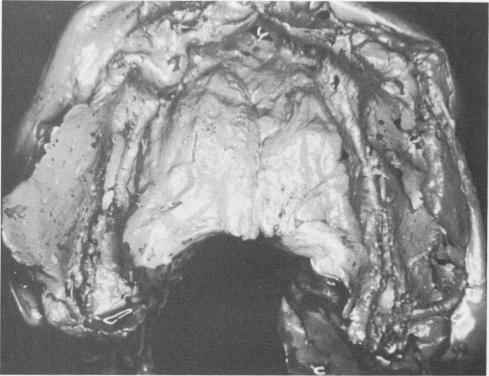

Fig. 11-187. The incision was made along the fibromucosal tissue covering the edentulous maxillary ridge.

The incision was made from maxillary tuberosity to maxillary tuberosity (Fig. 11-187). The tissues were retracted with a periosteal elevator to expose the entire hard palate. Grooves were then made in the bone and a rubber base impression taken with a specially designed tray. Some impression material was first loaded on the tray while still in a sticky form, while the rest was continously spatulated until it be-came putty-like. This portion was taken in the hands, forced into the shallow grooves, and molded over the ridges and palatal portion ; the loaded tray was immediately placed over it and held in position for about 10 minutes. When it hardened, it was removed (Fig. 11-188), and a bone bite was then taken with wax.

Fig. 11-188. An elastic impression was made including ex-posed palate and the posterior grooves.